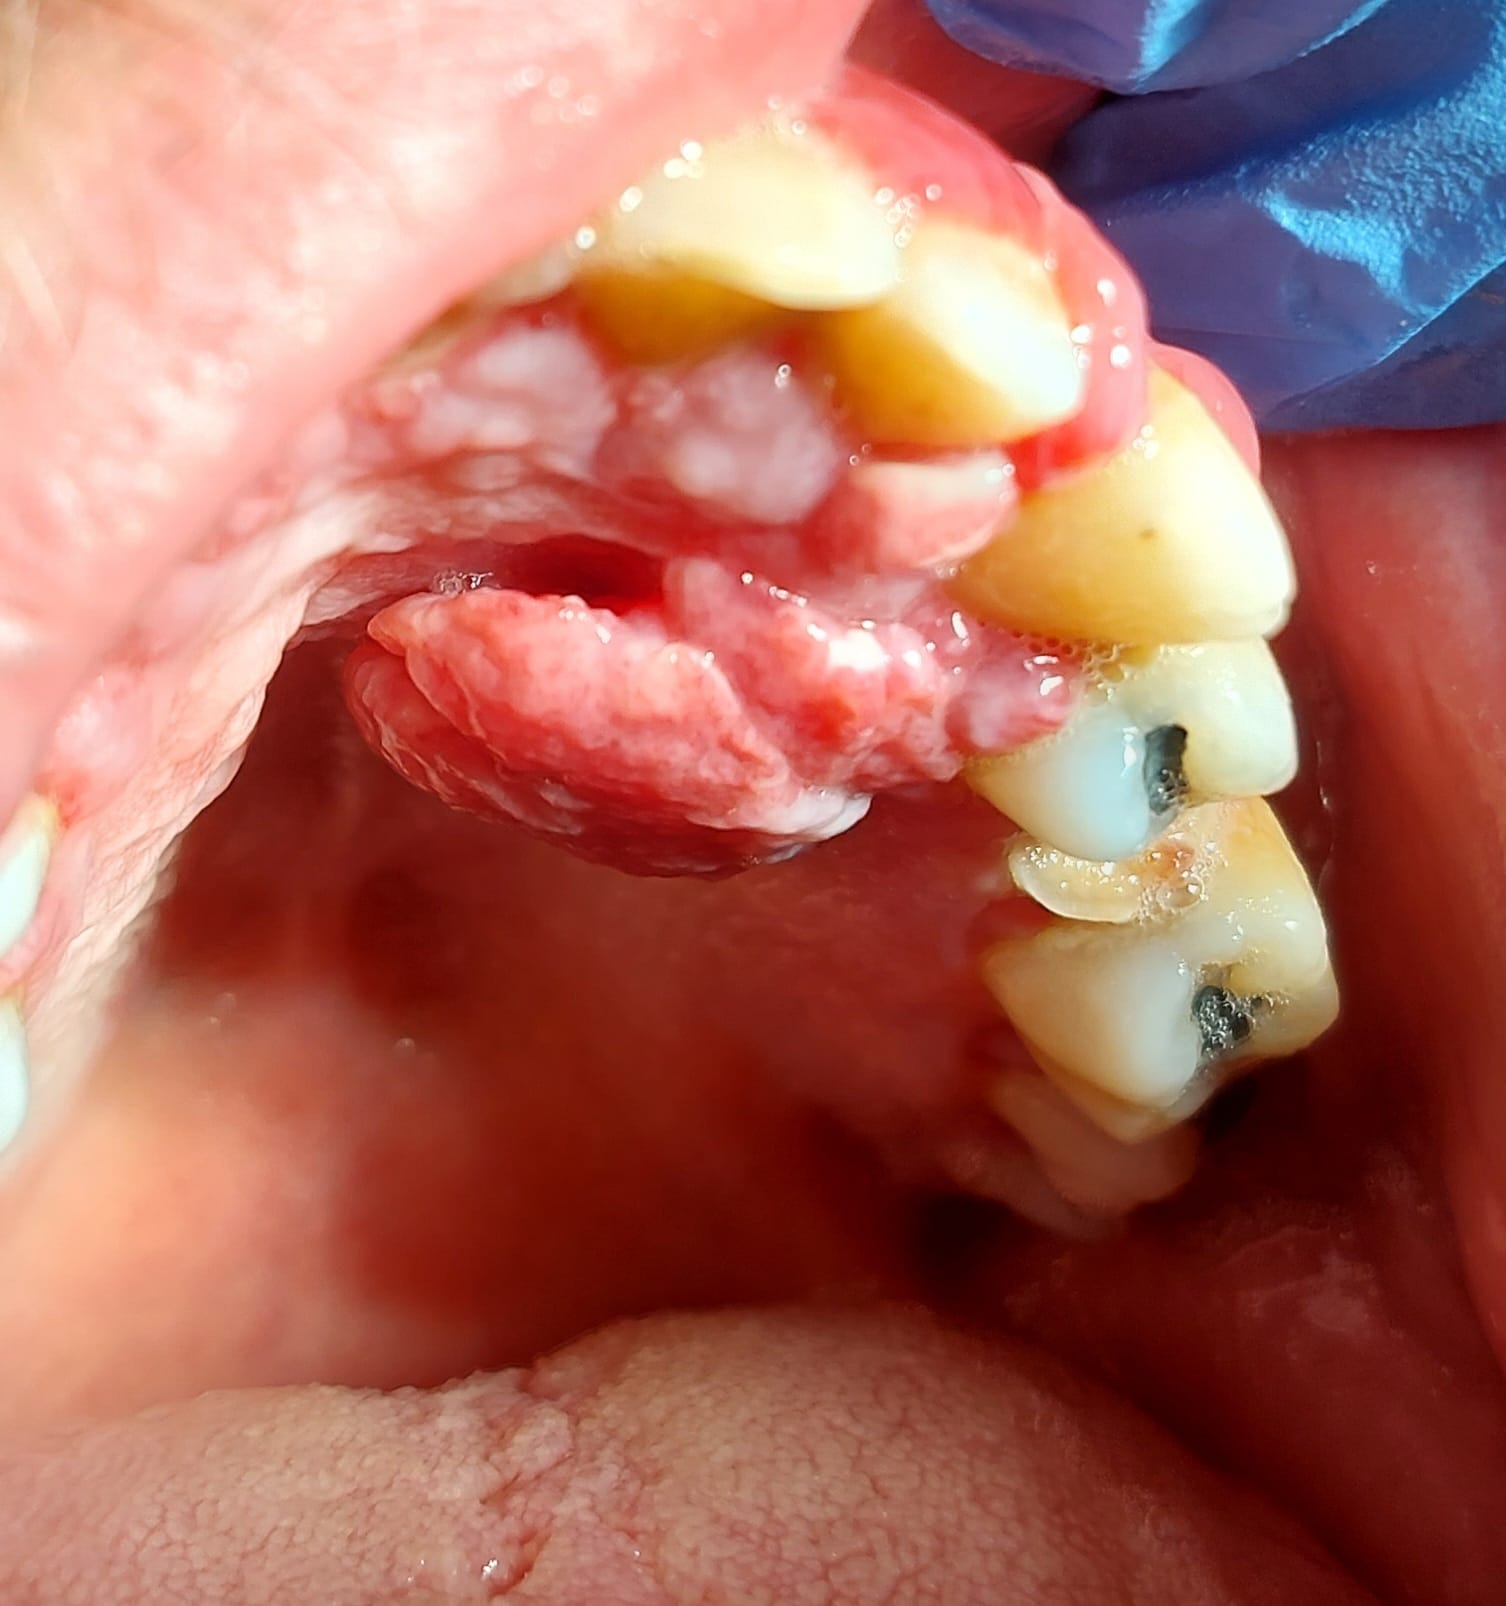

Patient de 31 ans, hépatite B depuis 1995 traitée par baraclude, à priori sans soucis mais pas de prise de sang depuis 6 mois. Également léger retard mental du à un syndrome lié à l'X.

Consulte pour hyperplasie gingivale apparue progressivement en 5 mois (RAS avant d'après lui), totalement indolores, pas de saignement sauf en insistant aux collets en gingivite.

Les 2 principales zones hyperplasiques dans le vestibule secteur 10 et palatin secteur 20 sont bien pédiculées et mobiles.

Voilà les photos.